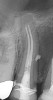

Fig 17. Retropreps and isthus filled. Courtesy of Dr. Sam Kratchman.

Figure 17

Fig 18. 20-month follow-up with BC putty shows complete healing. Courtesy of Dr. Sam Kratchman.

Figure 18

A patient presented with clinical symptoms and radiographic signs of post-endodontic disease (Figure 15). It was determined that the ledge on the mesial canals precluded retreatment and that an apicoectomy was to be performed. After locating the apicoectomy, it was possible to visualize both canals and an obvious isthmus between the two main canals (Figure 16). Retro-preparations were performed in the main canals, and the isthmus between them was grooved and the cavities filled with BC RRM-Putty (Figure 17). At the 20-month follow-up, the patient was asymptomatic and the radiograph showed complete healing (Figure 18).